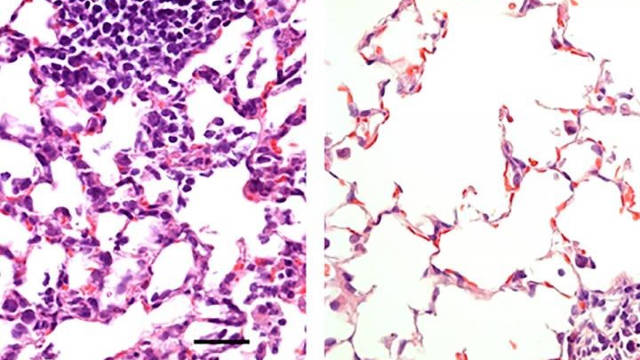

Comparación del tejido pulmonar de un ratón vacunado con el de uno que no lo está. EFE

Los investigadores compararon esta vacuna administrada a los ratones de dos maneras: en la nariz y a través de una inyección intramuscular. Mientras que la inyección indujo una respuesta inmune que previno la neumonía, no previno la infección en la nariz y los pulmones. Tal vacuna podría reducir la gravedad de Covid-19, pero no bloquearía totalmente la infección o evitaría que los individuos infectados propagaran el virus. Por el contrario, la vía de administración nasal previno la infección en las vías respiratorias superiores e inferiores (la nariz y los pulmones) lo que sugiere que los individuos vacunados no propagarían el virus o desarrollarían infecciones en otras partes del cuerpo.